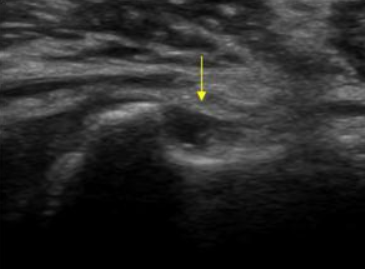

MRI, 초음파 등 영상검사로 힘줄 파열 정도를 평가합니다.